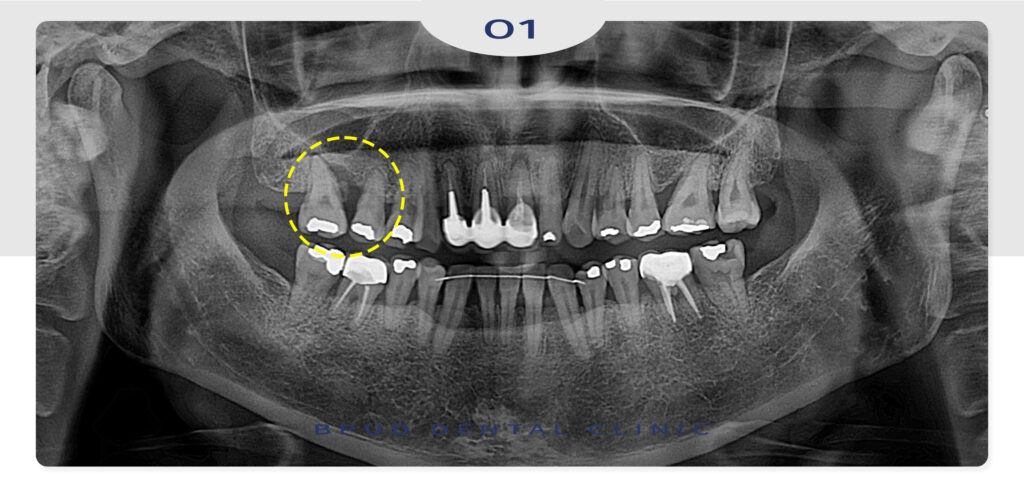

환자분께서는 위쪽 어금니 잇몸의 통증으로 인해

인터넷으로 검색 후 구강외과 전문의가 상주하고 있는

부평치과에 내원해 주셨습니다.

통증을 느끼고 계신 오른쪽 위 어금니 부위는

수직적인 골소실이 보였고, 큰 어금니 두개를

발치한 후 즉시 식립과 동시에 심한 염증으로

녹아 있는 잇몸뼈의 회복을 위해

상악동 거상술을 통한 뼈이식도 함께

진행하기로 하였습니다.